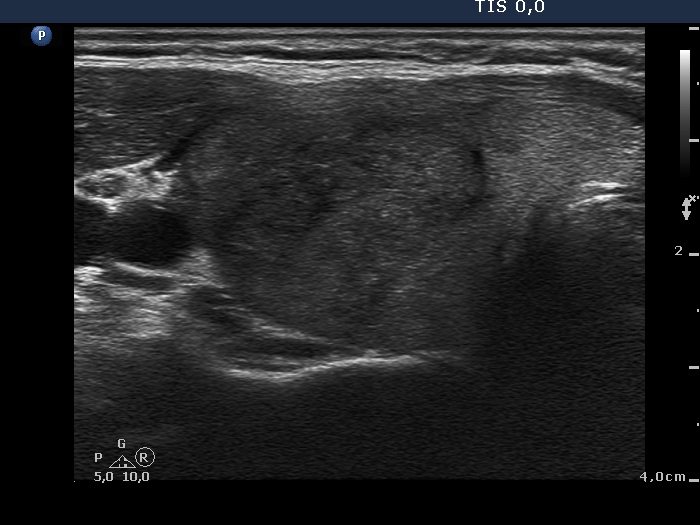

Initial examination (1st and 2nd rows of images):

Clinical presentation: a 50-year-old woman was referred for an evaluation of neck pain localized to the right thyroid and fever.

Palpation: the right thyroid was painful and hard.

Laboratory examination: hyperthyroidism (TSH 0.01 mIU/L, FT4 43.4 pM/L), CRP 18.3 mg/L.

Ultrasonography: there were multiple hypoechogenic areas with ill-defined borders in both lobes, primarily in the right one. The vascularization was decreased.